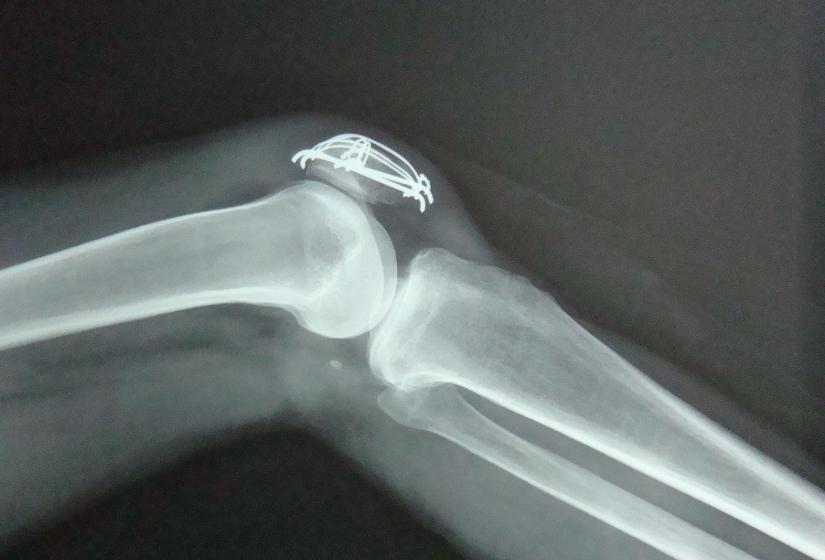

膝关节里有一个封闭的关节腔,关节腔里有少量的关节滑液。

滑液是由滑膜分泌的一种能润滑关节、减少摩擦、营养软骨的透明粘质液体。正常情况下,膝关节的滑液大概在10~20毫升。但如果关节受损、滑膜受到刺激,滑液的吸收和分泌就会受到影响,在关节腔里形成了积液。